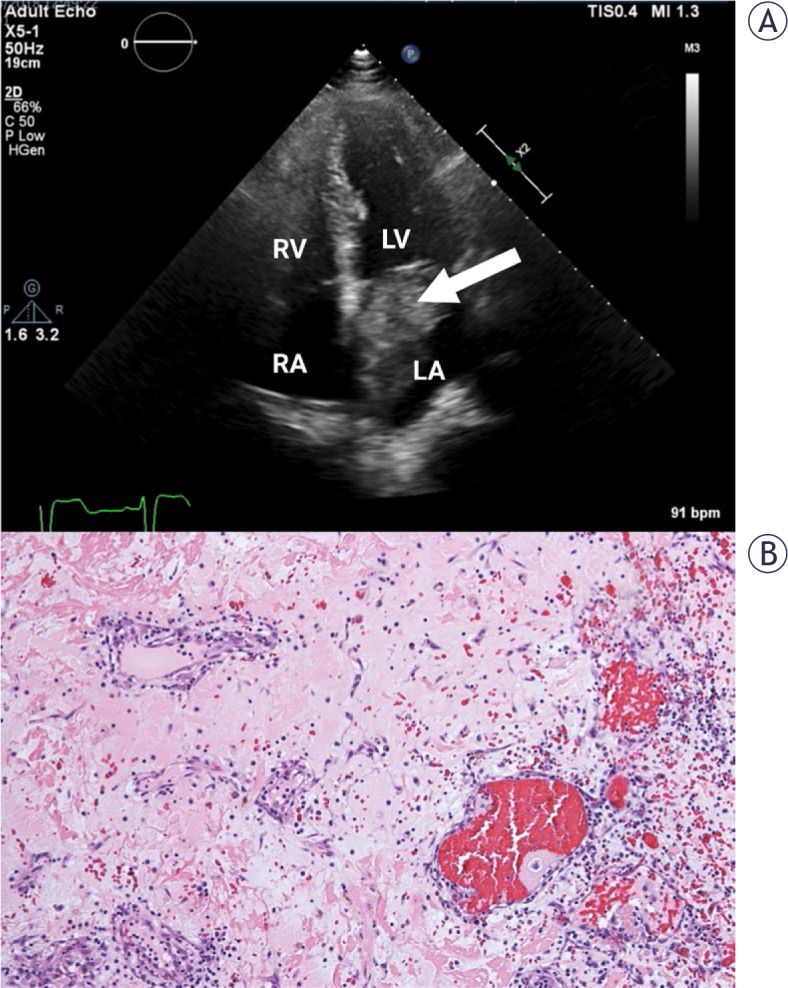

Background: The differential diagnosis of cardiac myxomas (CM), the most common benign primary cardiac tumors, is broad and a thorough diagnostic workup is required to establish accurate diagnosis prior to surgical resection. Transthoracic echocardiography (TTE) is usually the first imaging modality used for diagnosis of suspected CM. In a single tertiary centre study, we sought to determine the accuracy, sensitivity, and specificity of TTE in the diagnosis of CM and to determine echocardiographic characteristics indicative of CM.

Results: After diagnostic workup, 53 (73%) patients were treated surgically at our institution. Based on preoperative TTE, patients were divided into a CM group (n=45, 85%) and non-myxoma (NM) group. Of the 53 pathohistological specimens obtained during surgery, 39 (73%) were CM. The sensitivity and specificity of preoperative echocardiography were 97% and 50%, respectively. The overall accuracy was 85%. All NM tumors were found in an atypical location and 72% of CM were found in a typical position in the left atrium (p < 0.001). Tumors in NM group were significantly smaller than CM (24.3 ± 13.2 mm vs. 37.9 ± 18.3 mm, p = 0.017).

Conclusions: Our study confirms very good accuracy of TTE in the diagnosis of CM. The most important echocardiographic characteristics to differentiate between CM and tumors of different etiology are tumor location and size. Smaller tumors presenting at an atypical location are less likely to be diagnosed as CM, and these require additional imaging modalities for accurate diagnosis.